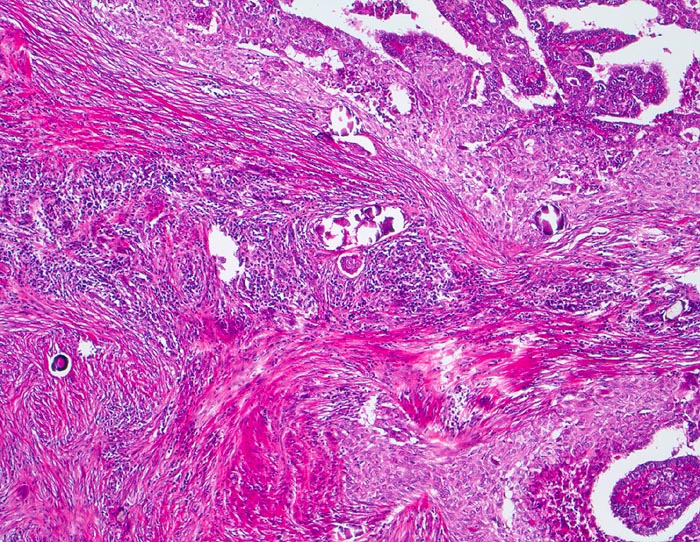

papilläres Schilddrüsenkarzinom diffus sklerosierende Variante

Infiltration der Schilddrüse durch ein papilläres Karzinom mit teils epidermoider Architektur. Auffällige Stromasklerose mit lymphozytärem Entzündungsinfiltrat. Zahlreiche Psammomkörperchen.

Das diffus sklerosierende papilläre Karzinom ist gekennzeichnet durch eine diffuse Infiltration der gesamten Schilddrüse mit Lymphangiosis carcinomatosa begleitet von einer deutlichen Sklerose und chronischen Entzündung. Dieser Tumortyp tritt bevorzugt bei jüngeren Patienten auf und hat eine schlechte Prognose. Plattenepithelmetaplasien treten in bis zu 7% der Schilddrüsenkarzinome auf.